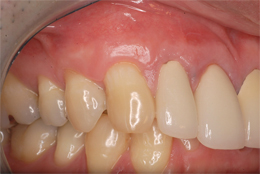

結合組織による根面被覆症例

-

- 主訴

- 右上3番がしみる

- 治療内容

- 右上3の歯頸部過度なブラッシングにより歯肉退縮したもので、右上口蓋より結合組織を採取し、歯根露出部に移植

- 治療費用

- CTG:60,000円(税別)

- 治療期間

- 術後3ヶ月の状態